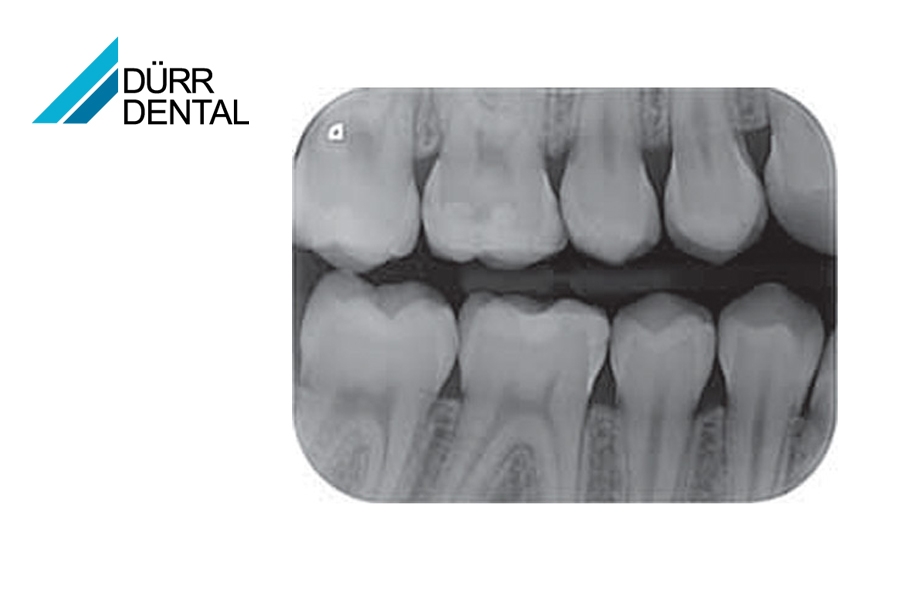

Grazie alla tecnologia PCS, VistaScan Mini è in grado di visualizzare in modo affidabile lesioni cariose di grado D1 e strumenti endodontici fino a ISO 06. Con 22 coppie di linee/mm e una scala di grigi a 16 bit (65.536) è all'avanguardia.